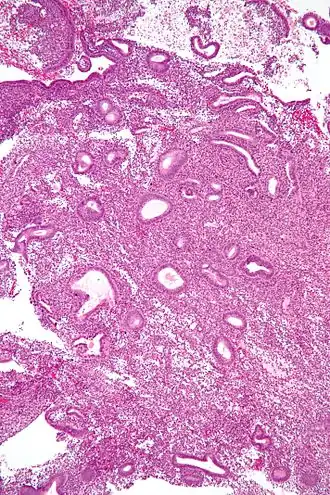

![]() Micrograph showing an endometrial biopsy with simple endometrial hyperplasia, where the gland-to-stroma ratio is preserved but the glands have an irregular shape and/or are dilated. H&E stain. | |